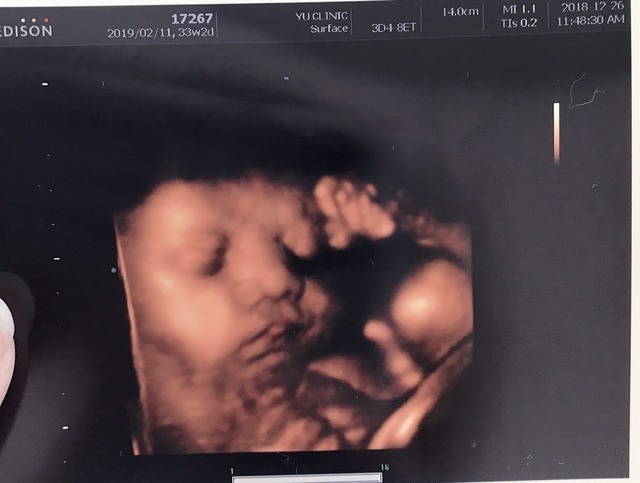

33週2日(33w2d・不明)|かりーーの さん(29歳)

エコー写真撮影時のエピソード:

大きくなってきて、顔がはっきり映るようにはなってきたけれど、大きくなるごとに全身が映らず、成長していることが目に見えて分かるのでうれしかったことを覚えています。

いつもはエコー写真を楽しみにしている旦那さんも、動いている姿が見たくて仕事を休んでいました。